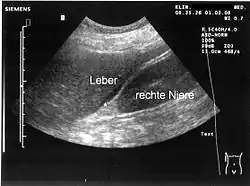

Sonografie

Die Ultraschalluntersuchung des Bauches erbringt meist freie Flüssigkeit und/oder freie Luft in der Bauchhöhle. Sichtbar wird hierbei auch die verminderte Motilität (Eigenbewegung) des Darmes. In vielen Fällen gelingt es, mit der Sonografie die Ursache der Peritonitis (Gallenblasenperforation, Dickdarmmileus mit Perforation, Pankreatitis etc.) einzugrenzen.